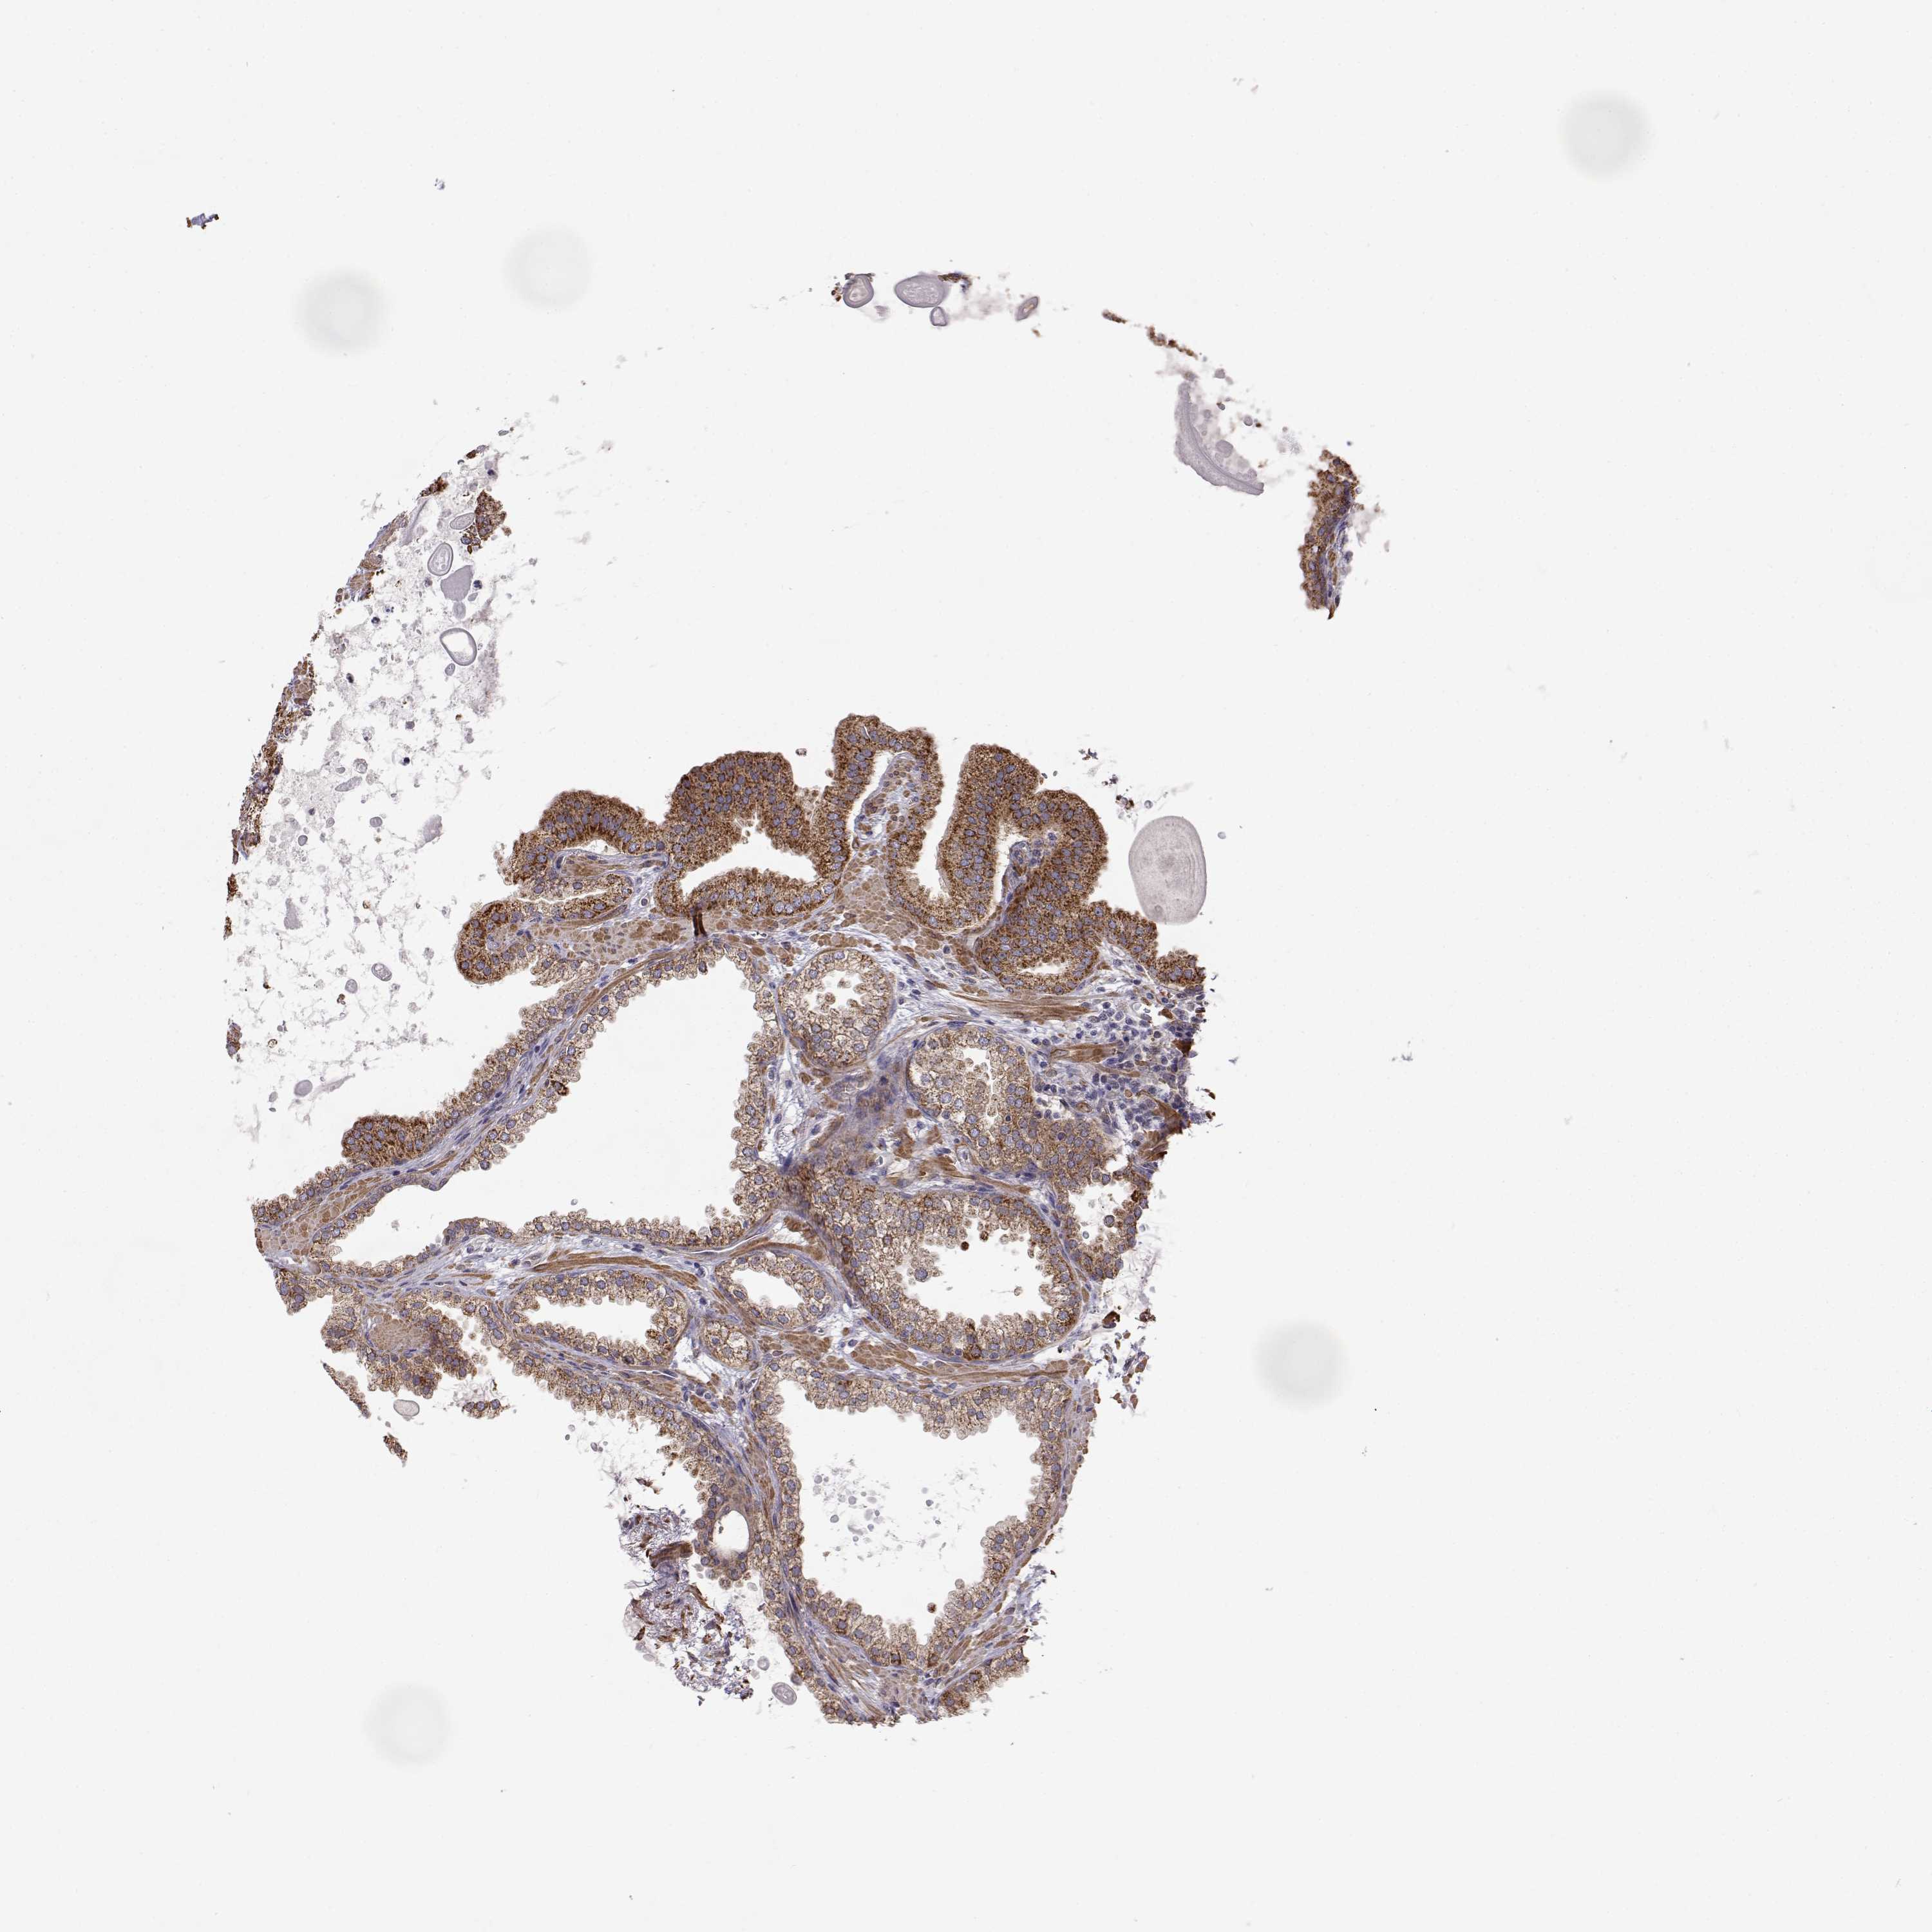

PROSTATE CANCER - Protein expressioni

A mouse-over function shows sample information and annotation data. Click on an image to view it in a full screen mode. Samples can be filtered based on level of antibody staining by selecting one or several of the following categories: high, medium, low and not detected. The assay and annotation is described here.

Note that samples used for immunohistochemistry by the Human Protein Atlas do not correspond to samples in the TCGA dataset.

Antibody stainingi

Antibody staining in the annotated cell types in the current human tissue is reported as not detected, low, medium, or high, based on conventional immunohistochemistry profiling in selected tissues. This score is based on the combination of the staining intensity and fraction of stained cells.

Each image is clickable and will lead to virtual microscopy that enables deeper exploration of all samples and also displays staining intensity scores, fraction scores and subcellular localization as well as patient and tissue information for each sample.

Antibody HPA073653

Staining

High

Medium

Low

Not detected

Intensity

Strong

Moderate

Weak

Negative

Quantity

>75%

75%-25%

<25%

None

Location

Nuclear

Cytoplasmic/membranous

Cytoplasmic/membranous,nuclear

Adenocarcinoma, High grade

Adenocarcinoma, NOS

Adenocarcinoma, Low grade